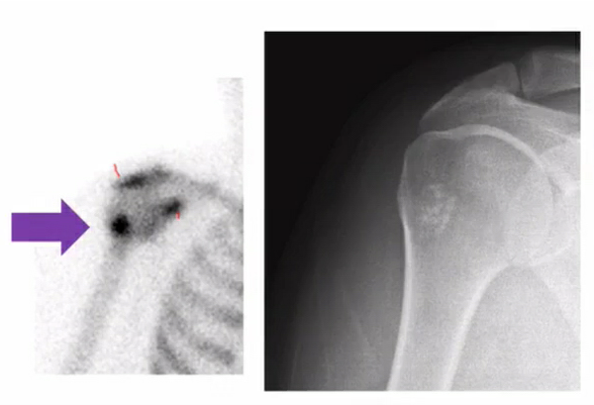

osteosarcoma in a kid